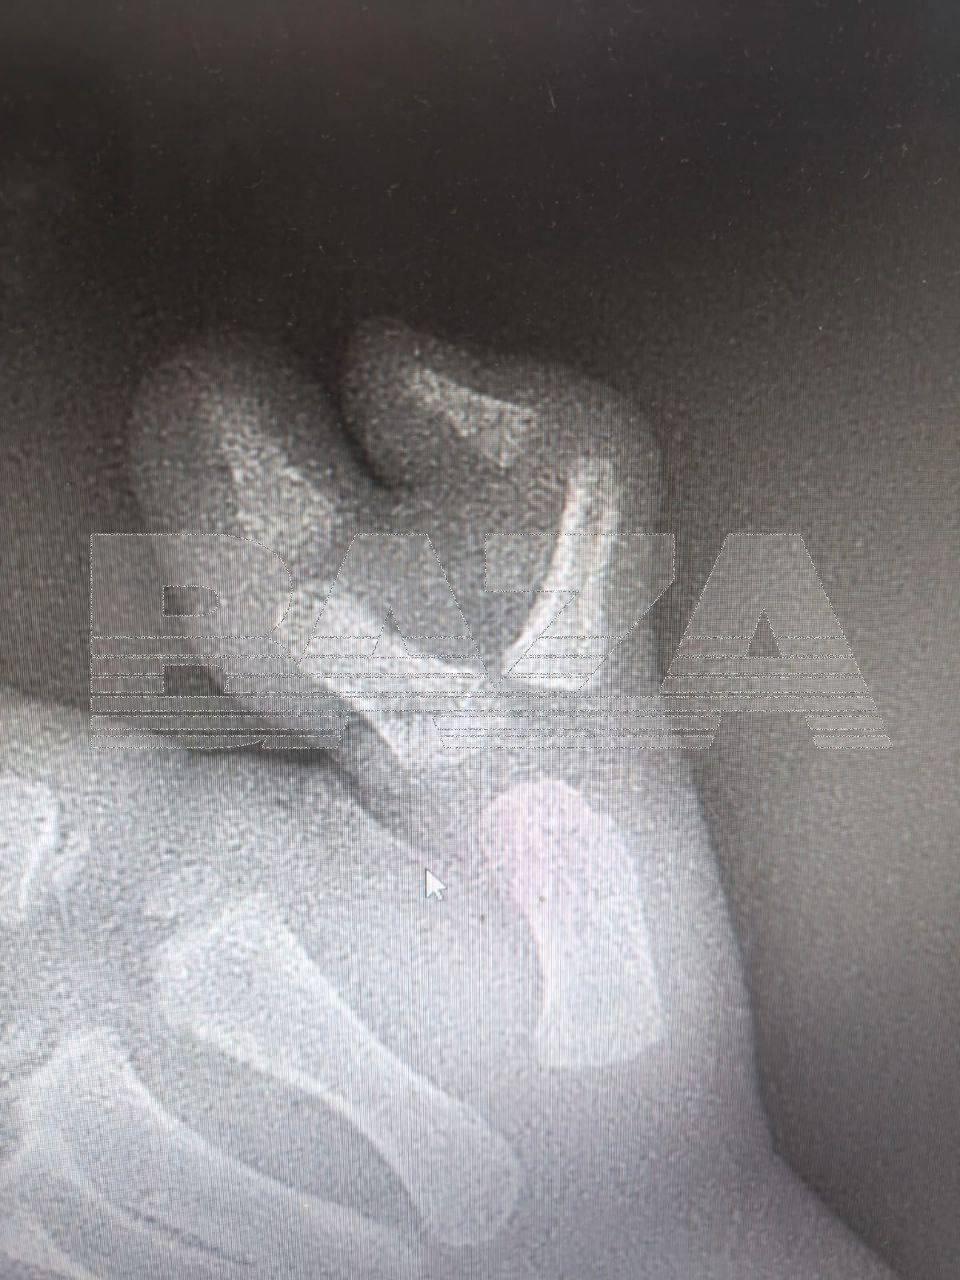

Малыша прооперировали в Московской областной детской клинической травматолого-ортопедической больнице. Хирурги отрезали палец и создали анатомически верное строение сустава. У ребёнка впереди осталось ещё одна операция — по удалению металлического стержня.